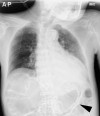

Emphysematous gastritis and gastric emphysema are different diseases. Sometimes, we treat the diseases without distinguishing them clearly because both are rare, and the mortality rate of emphysematous gastritis cases is high (55%). Gastric emphysema is more well known than is emphysematous gastritis after percutaneous endoscopic gastrostomy (PEG) placement (80%). Particularly, it is a self-healing disease, and treatment with antibiotics is not required. CT is commonly used to diagnose emphysematous gastritis and gastric emphysema. The amount of radiation exposure is a concern for performing multiple CTs following air disappearance in the gastric wall. Here, we report the case of a 92-year-old man with gastric emphysema after PEG. It was useful to follow-up the patient by performing radiographic examination, and the disease was managed conservatively without antibiotic administration. We report that distinguishing gastric emphysema from emphysematous gastritis was necessary. Moreover, performance excessive tests and treatments should be avoided.